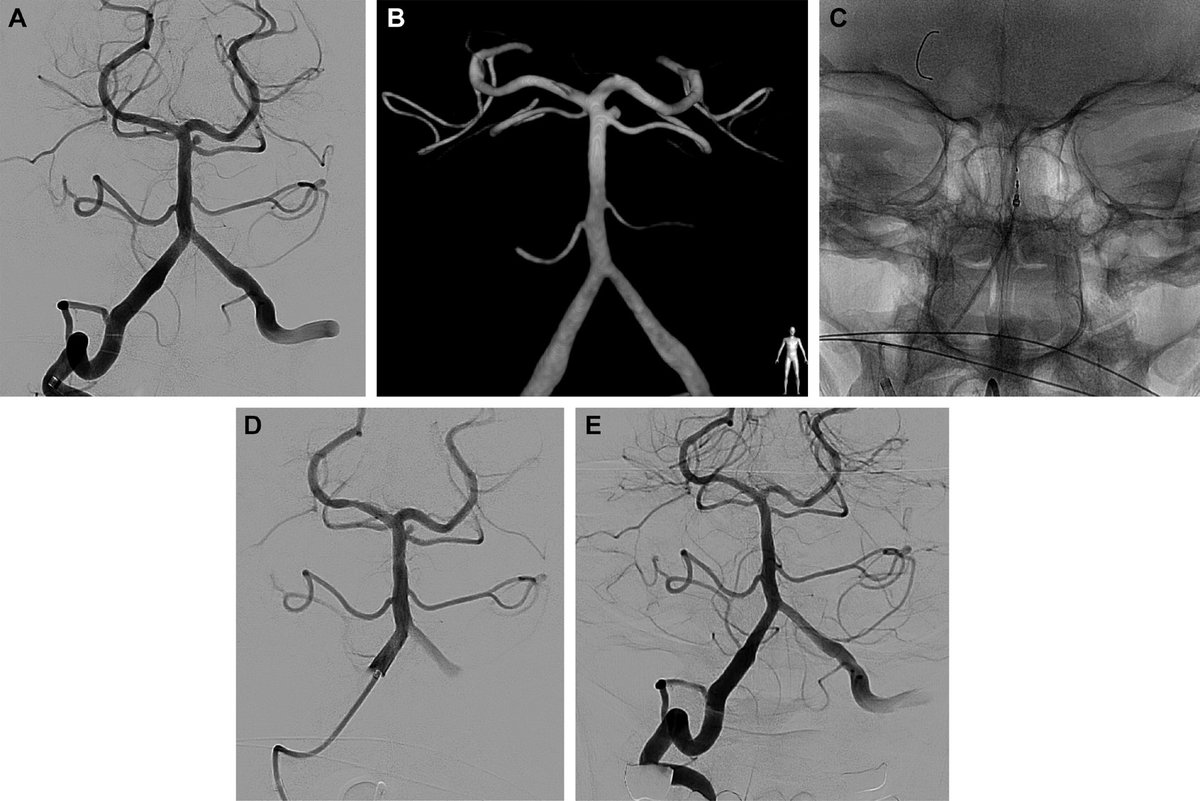

Before and after. Symptomatic distal ICA stenosis following placement of Balloon mounted stent Stent here needs good radial force but trackable around petrous carotid. Balloon mounted stent fits role well #carotidstenosis #stroke #Neurosurgery

Before and after. Symptomatic distal ICA stenosis following placement of

Balloon mounted stent

Stent here needs good radial force but trackable around petrous carotid. Balloon mounted stent fits role well

#carotidstenosis #stroke #Neurosurgery